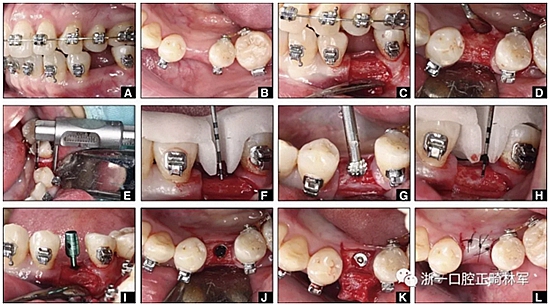

圖12.將種植體植入正畸產(chǎn)生的間隙中的步驟:A,將下頜左側(cè)第二前磨牙向遠(yuǎn)中移動(dòng)以在前磨牙之間產(chǎn)生間隙; B,種植部位的咬合面觀(guān); C,一個(gè)水平切口和兩個(gè)垂直切口,距相鄰牙齒1.5mm的距離; D,暴露的牙槽嵴的咬合面觀(guān); E,測(cè)量牙槽嵴的寬度約6mm; F,手術(shù)導(dǎo)板顯示預(yù)備冠頸部的位置距離骨牙槽嵴頂僅1毫米; G,用球鉆修整牙槽嵴; H,建立3mm從手術(shù)導(dǎo)板的頸部輪廓到骨嵴的距離,以實(shí)現(xiàn)必要的生物學(xué)寬度; I,引導(dǎo)針顯示了截骨的角度; J,3.5×10mm種植體完全置于骨內(nèi); K,一個(gè)覆蓋螺帽就位; 和L,縫合。